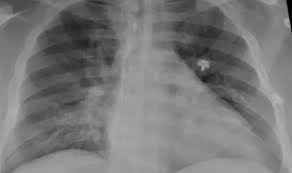

La neumonía bilateral “es una de las mayores complicaciones de los pacientes con Covid, es una enfermedad que afecta los dos pulmones. En casos graves debe internarse ya veces puede ser causa de muerte”, alerta Ana Putruele, jefa de la División de Neumología del Hospital de Clínicas.

En la actualidad este tipo de neumonía en general se ve en casos de coronavirus y constituye el 80% de las internaciones. También se presenta en menores de 2 años, en mayores de 65 y en portadores de enfermedades crónicas, cardíacas y asociadas a tabaquismo suele generar riesgo de mortalidad llevando a insuficiencia respiratoria severa o distress respiratorio que requiere de oxigenoterapia o si es muy grave asistencia respiratoria mecánica ”, Comenta la profesional.

La neumonía es una infección que afecta a los pulmones, de forma aguda, generando síntomas como fiebre, tos, dolor torácico y falta de aire. “Cuando baja la temperatura se duplican o triplican las posibilidades de infecciones pulmonares. Por otro lado, las personas deben estar más tiempo en ambientes cerrados que favorecen la transmisión de enfermedades virales”, comenta Putruele.